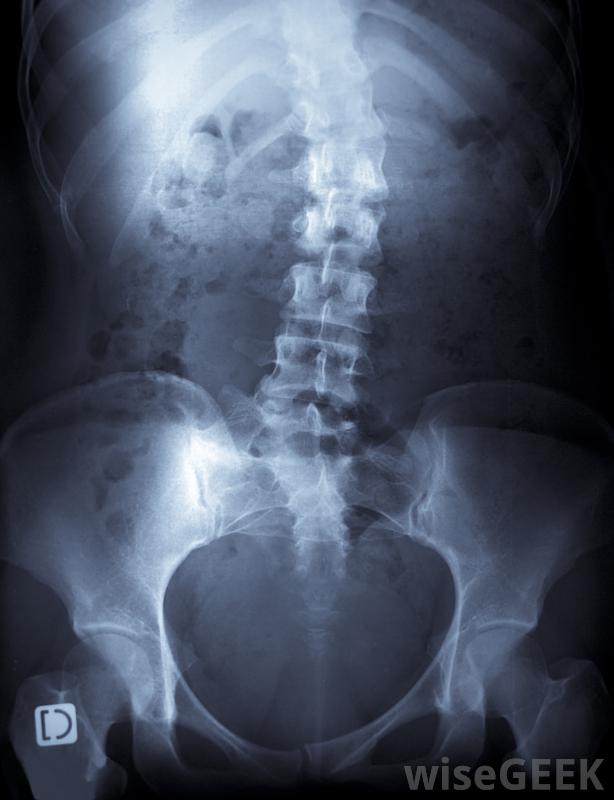

脊柱侧凸会导致脊柱弯曲。

脊柱侧凸物理疗法是一种保守的治疗脊柱侧凸的方法,脊柱侧凸是一种以脊柱弯曲为特征的骨骼疾病,物理疗法可以与其他治疗方法相结合,也可以单独使用,根据患者的情况和推荐的治疗方法。医学界对脊柱侧凸的治疗效果存在一些争论。一些研究表明,物理疗法对某些类型的病例有帮助,在脊柱侧凸的物理治疗中可以采用按摩和手法,也就是说,脊柱弯曲的原因是未知的。在童年或青春期早期,脊柱开始向一侧或另一侧弯曲,脊柱侧弯会变得非常严重。脊柱侧凸的治疗通常集中在阻止曲度的发展上。治疗方案的使用取决于具体病例的具体情况。一般来说,干预越快,患者可能的结局越好,这也是为什么建议对幼儿进行脊柱侧凸检查,以便尽早发现脊柱弯曲。